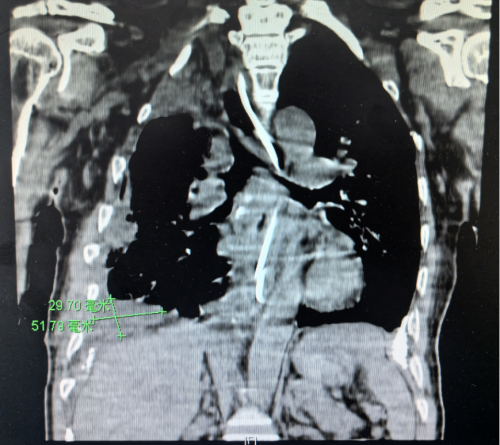

术后CT

袁跃西介绍,结核性胸膜炎和结核性脓胸是临床常见的结核病之一,临床表现主要是胸腔积液,可伴有发热、胸痛、咳嗽、咳痰及活动后喘息等症状。早期脓胸可通过胸腔穿刺引流和规范的抗结核治疗而痊愈。若治疗不及时,胸腔积液包裹,胸膜增厚形成纤维板,则会发展为慢性结核性脓胸,需手术治疗。